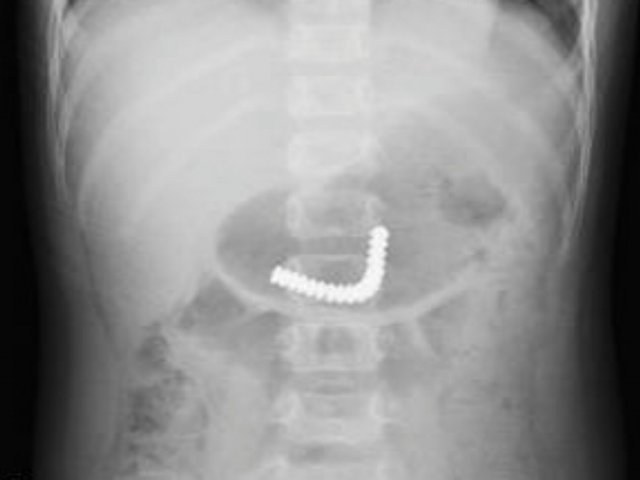

18 viên nam châm kết chùm trong ruột bé trai

Bé trai gần ba tuổi, nuốt 18 viên nam châm trong máy massage mắt của mẹ, được đưa vào bệnh viện cấp cứu phải cắt, nối ruột.